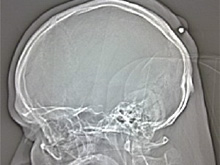

Мужчина прожил 5 лет с пулей в голове26.08.10 13:13 Прочтений новости 1063 Общество Немецкие врачи провели операцию по извлечению пули из головы 35-летнего жителя Германии, который проходил с ней около пяти лет. Как сообщается, мужчина не испытывал никаких неудобств, и обратился к врачам для того, чтобы обследовать возникшую на затылке опухоль.

Скорее всего, мужчина получил пулю в новогоднюю ночь в 2004 или 2005 году. Немец шел по улице и почувствовал сильный удар в затылок, но не придал ему никакого значения, поэтому и не стал обращаться в клинику. По мнению полицейских, в мужчину попала шальная пуля, которая была выпущена из оружия в честь празднования Нового года. Немцу несказанно повезло, т.к. пуля 22 калибра застряла в коже головы и не попала в головной мозг. Комментарии (всего 0)